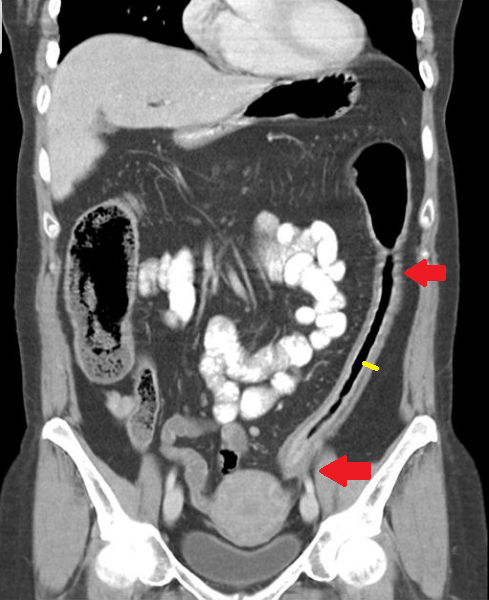

Bu ülseratif kolit hastasında da kırmızı oklarla işaretlenen barsak bölümü duvarındaki bariz kalınlaşma, düzleşme, haustralarda kayıp ile içi boş silindirik bir boru halini almış. Sarı çizgi duvarın ne kadar kalınlaştığını gösteriyor. Bu görünüme “kurşun boru” bulgusu adı veirlmiş.